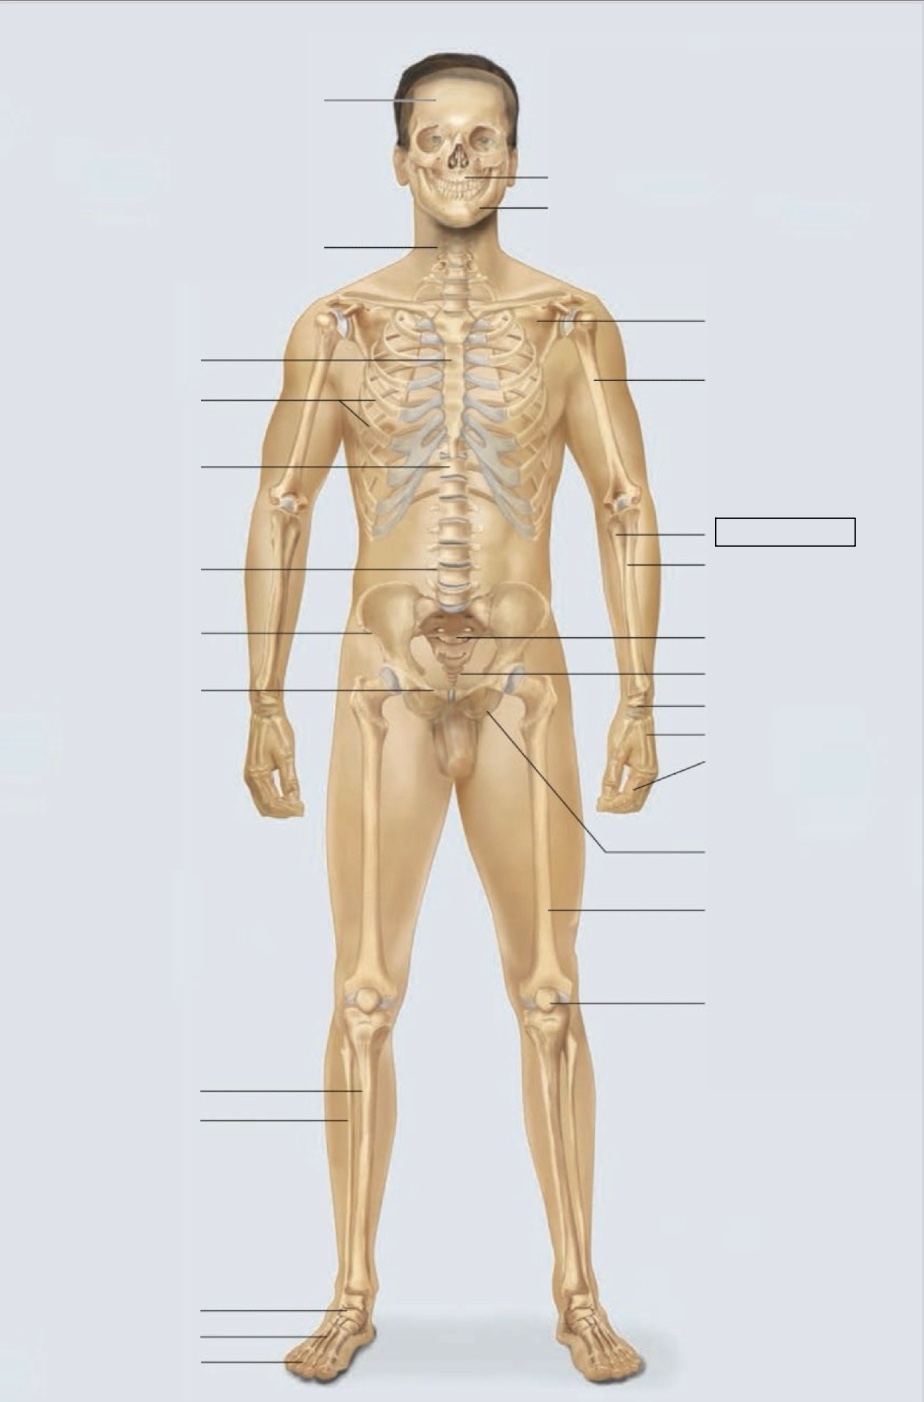

maxilla

mandible

scapula

humerus

ulna

radius

sacrum

coccyx

carpals

metacarpals

phalanges

ischium

femur

patella

phalanges

metatarsals

tarsals

fibula

tibia

pubis

ilium

lumbar vertebrae (L4)

thoracic vertebrae (T11)

ribs

sternum

cervical vertebrae

skull